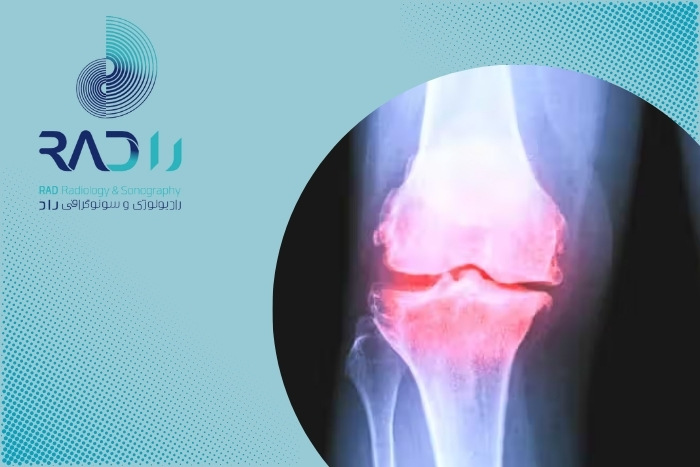

رادیوگرافی ساده یکی از رایجترین و در دسترسترین روشهای تصویربرداری مفاصل است. اما سؤال اصلی این است که آیا این روش میتواند آرتروز در مراحل اولیه را نشان دهد یا خیر. رادیولوژی درواقع استخوان را نشان میدهد نه غضروف را. چون آرتروز اولیه بیشتر از غضروف و بافت نرم شروع میشود رادیولوژی در این مرحله تغییرات آشکاری را نشان نمیدهد. تنها زمانی که فاصله مفصلی کم شود یا استخوان دچار استئوفیت گردد آرتروز در رادیولوژی قابل تشخیص میشود.

اگرچه رادیولوژی ساده در تشخیص آرتروز اولیه محدودیت دارد اما در مراحل بعدی بسیار کاربردی میشود. پزشک در مواردی مانند درد مزمن زانو یا دست، تغییر شکل مفصل، سابقه ضربه یا محدودیت شدید حرکتی رادیولوژی را تجویز میکند. رادیولوژی همچنین برای بررسی روند پیشرفت بیماری در طی زمان مناسب است. این روش به پزشک اجازه میدهد میزان تنگ شدن فضای مفصلی، وجود خارهای استخوانی و سفتی استخوان زیر غضروف را ببیند. حتی در شرایطی که آرتروز اولیه با سونوگرافی یا امآرآی تشخیص داده شده باشد انجام رادیولوژی برای تکمیل بررسی ساختاری مفصل ضروری است. اگر قصد انجام رادیولوژی در بلوار کشاورز را دارید میتوانید به مرکز تصویربرداری راد با تجهیزات پیشرفته مراجعه کنید.